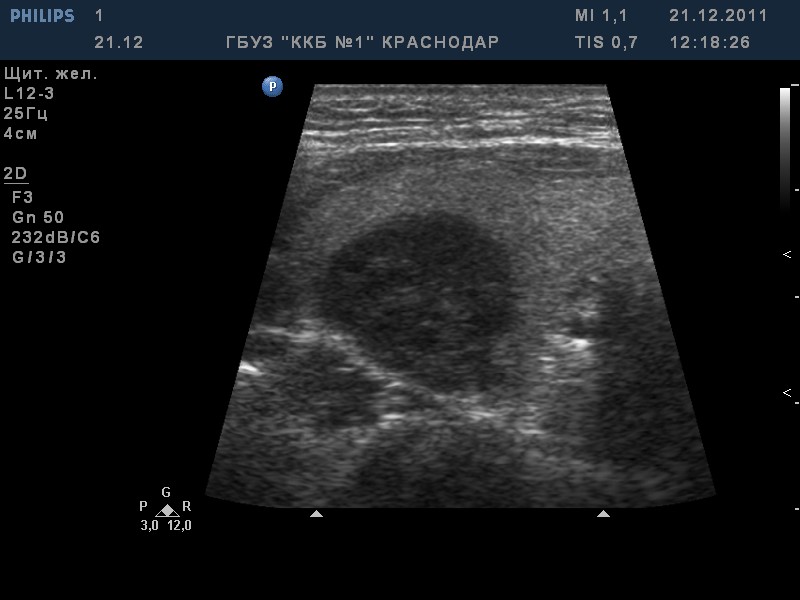

TI-RADS 5. Солидные узлы с “большими” признаками злокачественности для выполнения ПУНКЦИИ:

- солидные узлы более 1,0 см в диаметре: при наличии хотя бы одного “большого” признака злокачественности (рис. 4):

– значительно сниженная эхогенность;

– вертикальная пространственная ориентация образования;

– неровный контур образования: бугристый, микродольчатый, лучистый;

– наличие в опухоли микрокальцинатов;

Рис. 4. TI-RADS 5. Узлы ЩЖ размером >1,0 см (папиллярные раки): а, б – узлы значительно пониженной эхогенности с микрокальцинатами, с неровными микродольчатыми контурами; в – узел вертикальной пространственной ориентации, с нечеткими, неровными контурами, значительно сниженной эхогенности, с множественными микрокальцинатами; г – узел с микродольчатыми нечеткими контурами, неравномерно пониженной эхогенности, с микрокальцинатами; д – узел значительно пониженной эхогенности, вертикальной пространственной ориентации, с нечеткими, неровными (лучистыми) контурами; е – узел с нечеткими контурами, с множественными микрокальцинатами.